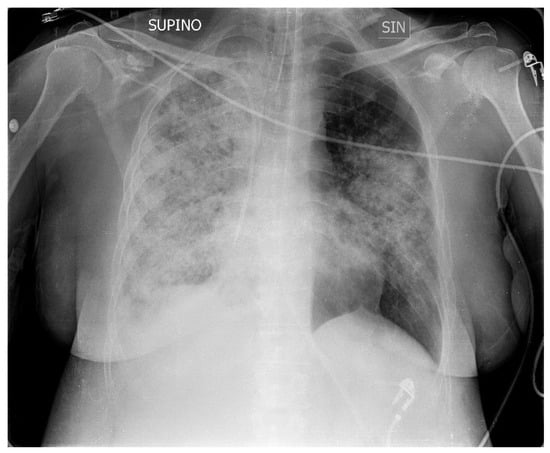

A 50-year-old patient with Down syndrome came to our ED with fever (38 °C), severe respiratory failure, tachypnea and dyspnea, an SpO2 of 82% with Venturi mask valves 15l/FiO2 60%, sinus tachycardia, blood pressure of 105/63 mmHg, and imaging of bilateral pneumonia in an X-ray of the chest, with greater involvement of the right lung (Figure 1). The patient came from the medical department of another hospital, and the symptoms had started about 10 days prior with a cough and low-grade fever. After seven days of home therapy with ceftriaxone and azithromycin for worsening symptoms, she was admitted to hospital with the diagnosis of bilateral interstitial pneumonia. Here, empiric therapy with meropenem, linezolid, and caspofungin was started, and supplemental oxygen was required.

Figure 1.

Chest X-ray upon admission to hospital shows bilateral pneumonia, with greater involvement of the right lung. SUPINO: supine; SIN: left.